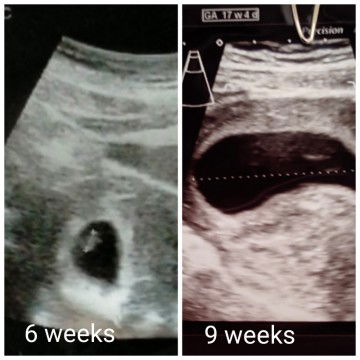

hamil 9 minggu janin tidak terlihat di usg. padahal saat 6 minggu janin sudah terlihat

sedih rasanya.. beberapa waktu lalu usg pas 6 minggu 4 hari, janin terlihat masih sangat kecil tp normal dalam usia kandungan 6 minggu dengan ukuran seperti itu. saat 8 minggu saya mengalami mual muntah yg sangat parah sampai masuk rawat di rs. kmrn jadwal saya rawat jalan sambil pemeriksaan kandungan. tapi di usg janin ga keliatan ?? detak jantungnya pun katanya ga ada. Padahal selama ini ga pernah ada flek sedikitpun keluar.. Saya sempat searching tentang kehamilan kosong, tp katanya kl kehamilan kosong pasti saat 6 minggu pun blm ada kelihatan janin nya. dan juga pasti keluar flek. sedangkan yg saya alami tidak seperti itu.. saya tidak mengeluarkan flek dan juga saat kandungan 6 minggu janin sudah terlihat.. dokternya menyarankan saya untuk makan dan banyak minum lalu kembali lagi 2 minggu untuk cek usg lagi. apa ada yg pernah mengalami hal seperti saya?